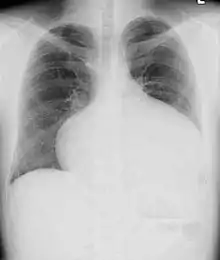

Adults with an uncorrected ASD present with symptoms of dyspnea on exertion (shortness of breath with minimal exercise), congestive heart failure, or cerebrovascular accident (stroke). They may be noted on routine testing to have an abnormal chest X-ray or an abnormal ECG and may have atrial fibrillation. If the ASD causes a left-to-right shunt, the pulmonary vasculature in both lungs may appear dilated on chest X-ray, due to the increase in pulmonary blood flow.[18]